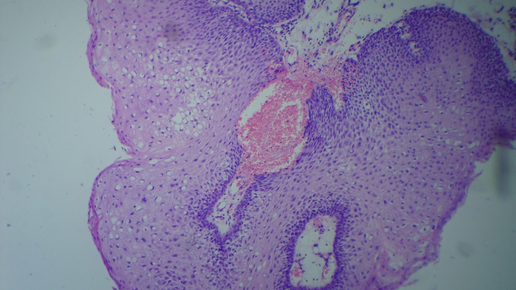

Часто используемые гистологические окраски

В статье описаны основные гистохимические окраски, используемые в практике гистологической лаборатории